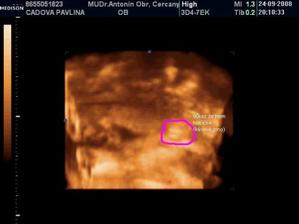

• 24.9.2008 – 4D ultrazvuk, potvrzena holčička